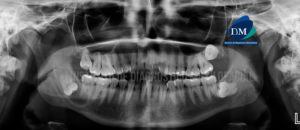

Paciente de sexo femenino de 40 años de edad acude al Instituto de Diagnóstico Maxilofacial para evaluación imagenológica de terceras molares. A la evaluación de